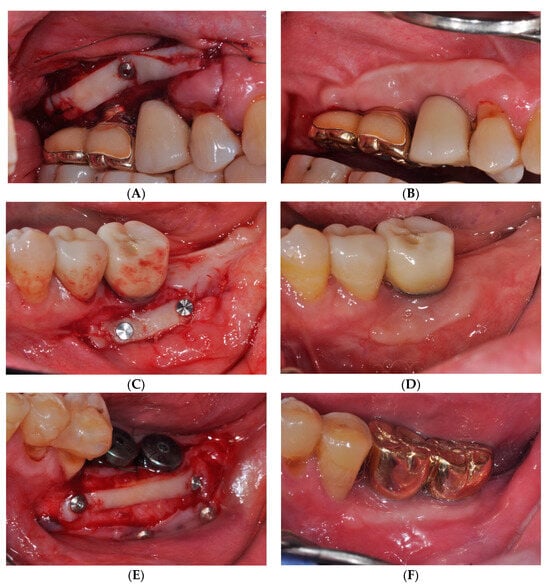

2.1. Surgical Procedures of the Simplified Free Gingival Graft Using Fixation Tacks (sFGG)

2.2. Case